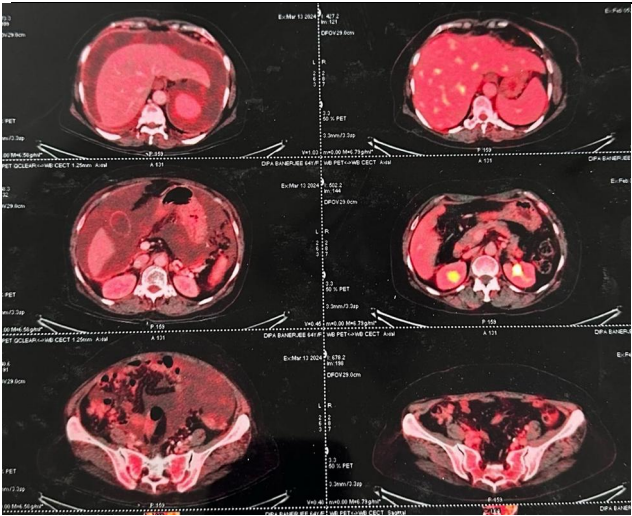

A 67-year-old female presented with abdominal pain, distension, and recurrent maliganant ascites over two months. She underwent therapeutic ascitic tapping at another hospital, draining 4 liters of fluid. PET-CT imaging revealed FDG-avid lesions in the bilateral adnexal regions, omental thickening, peritoneal deposits, and moderate ascites.

Fig 1

1. Imaging: PET-CT identified extensive metastatic involvement, including bilateral adnexal masses (largest 4.2 × 3.6 cm), peritoneal deposits, and omental caking.  [Fig.1]

First-line Therapy: The patient received six cycles of Cisplatin and Etoposide, leading to a significant response as noted on interim PET-CT scans [Fig 2]. However, disease progression was observed post-treatment.